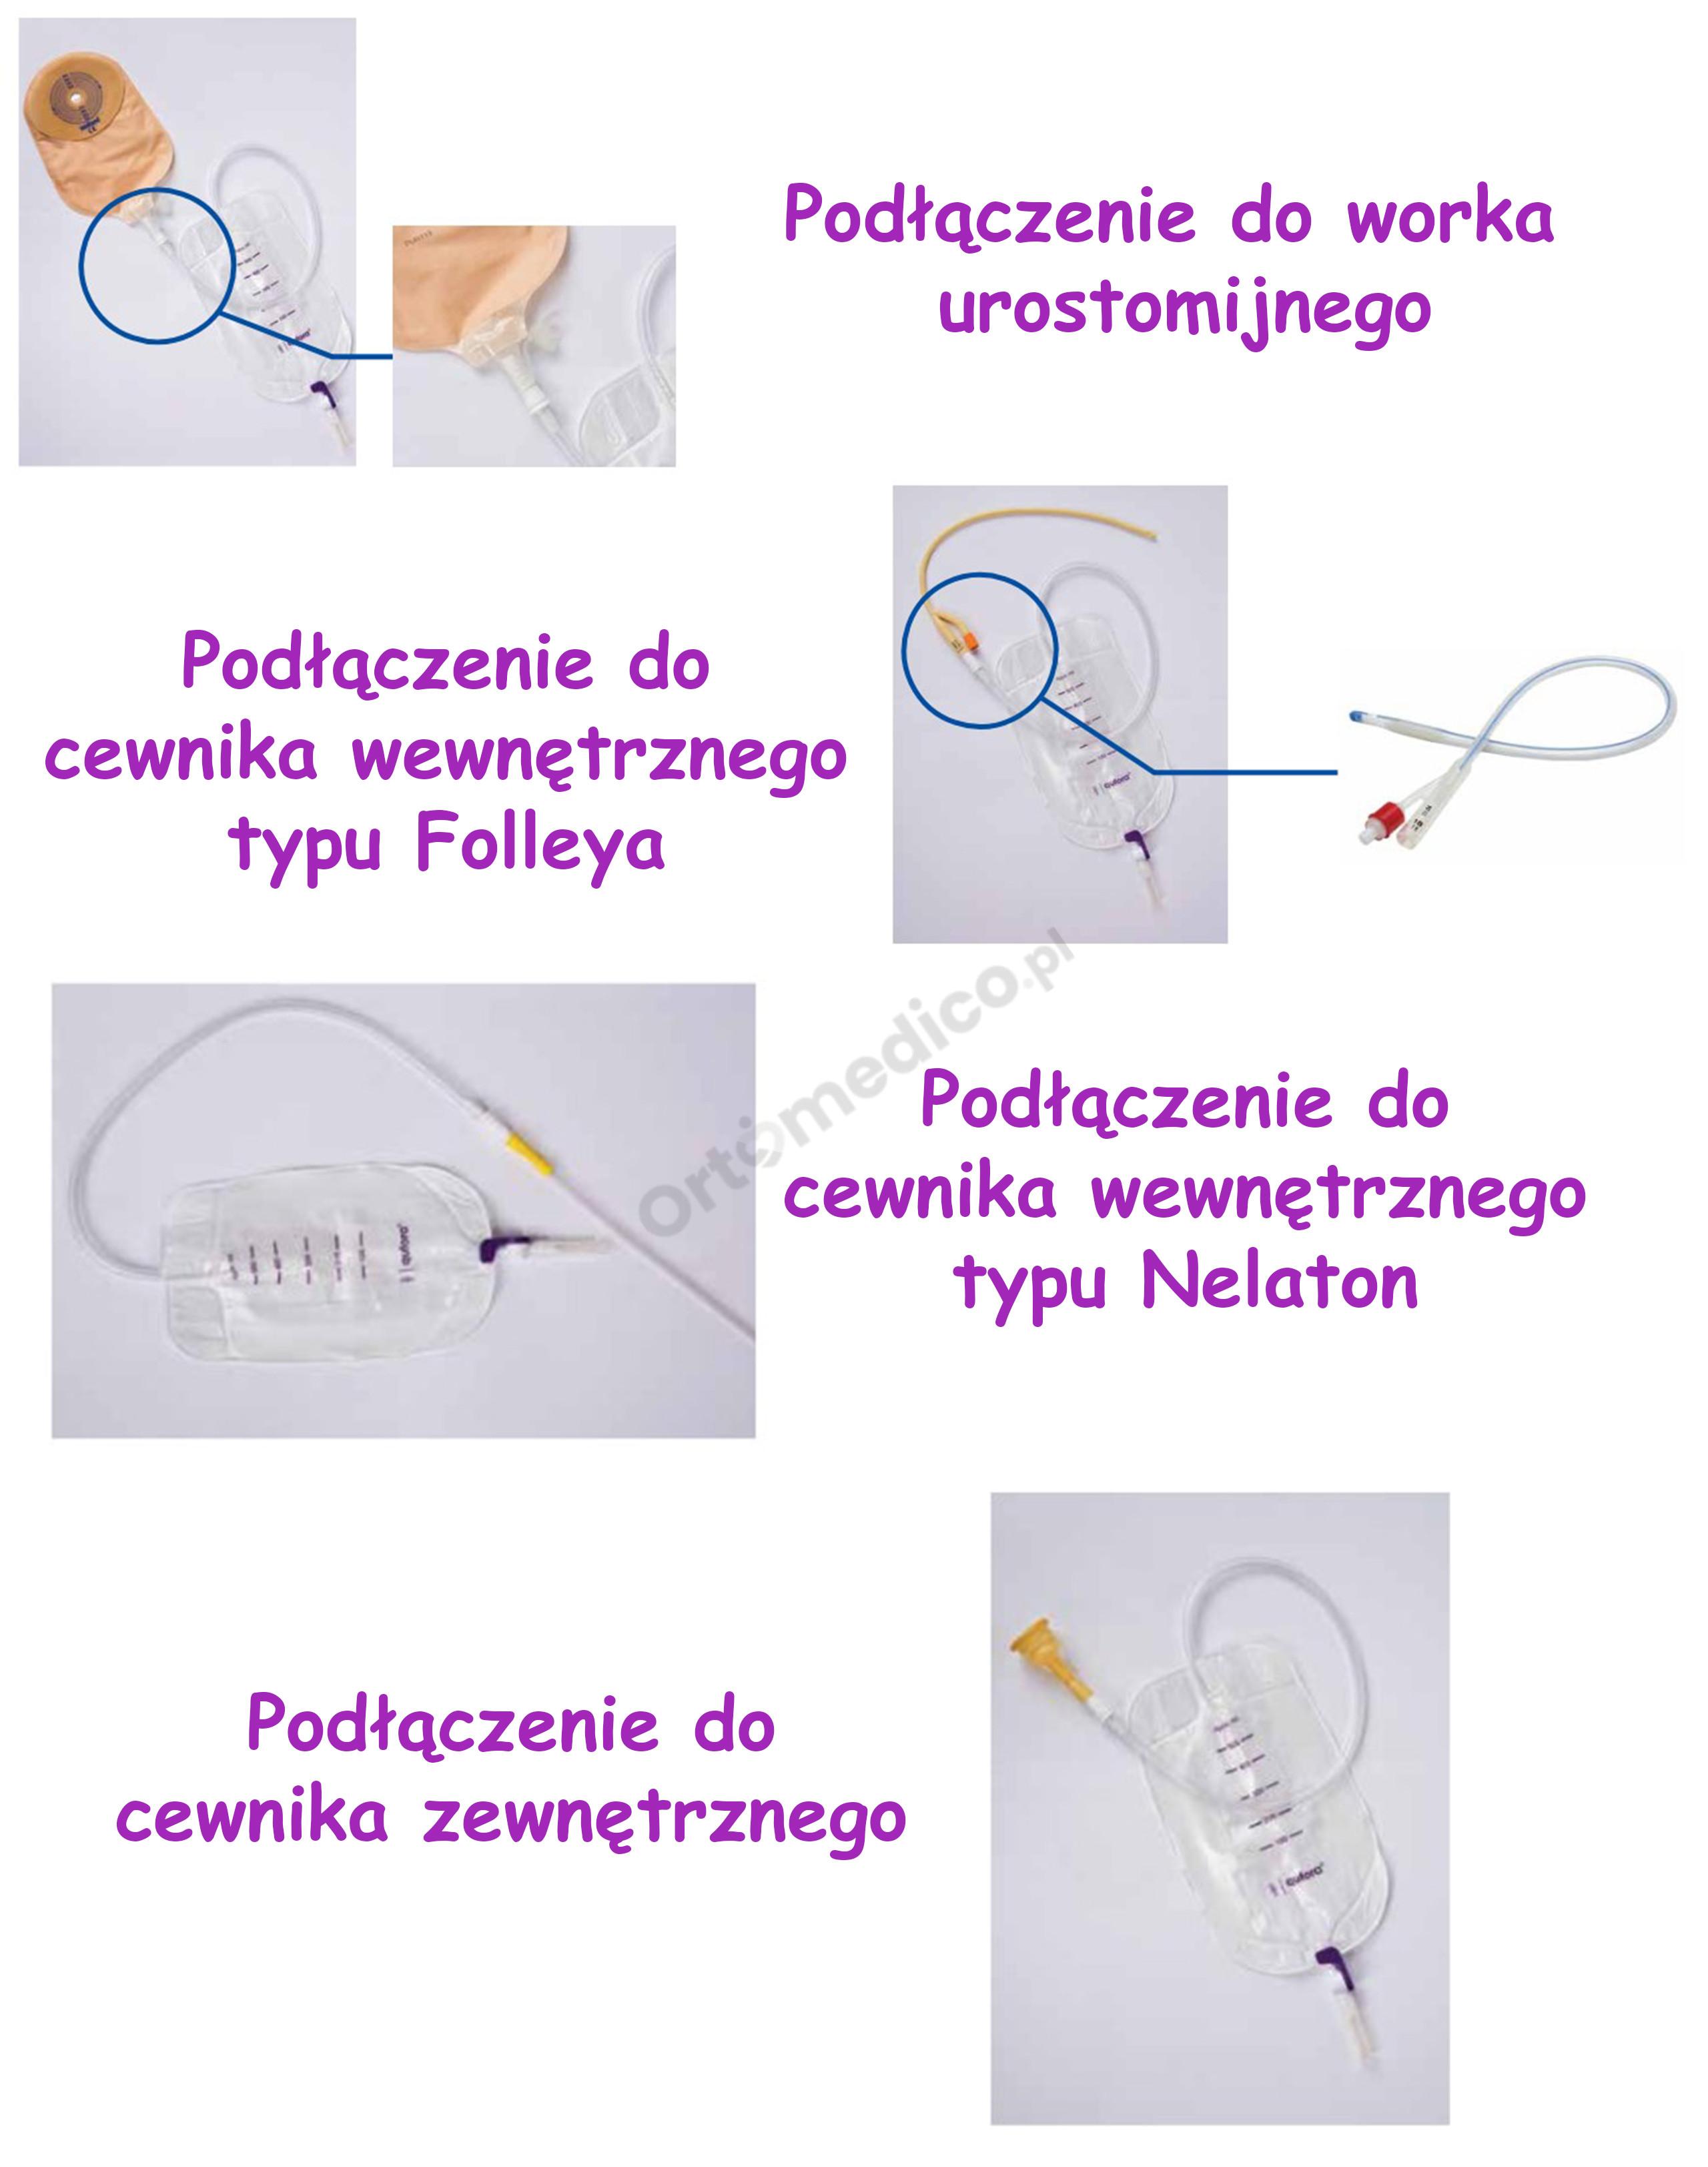

- Uniwersalny łącznik w kształcie stożka: Stożkowy łącznik umożliwia łatwe i szybkie podłączenie worka do różnych typów cewników wewnętrznych (urologicznych), zewnętrznych oraz worków urostomijnych. Zapewnia to wszechstronność i uniwersalność użytkowania.

- Uniwersalny łącznik w kształcie stożka: Stożkowy kształt łącznika umożliwia łatwe i bezpieczne podłączenie worka do różnych typów cewników (wewnętrznych, zewnętrznych) oraz worków urostomijnych. Jest on zaprojektowany tak, aby zapewnić pewne i szczelne połączenie.